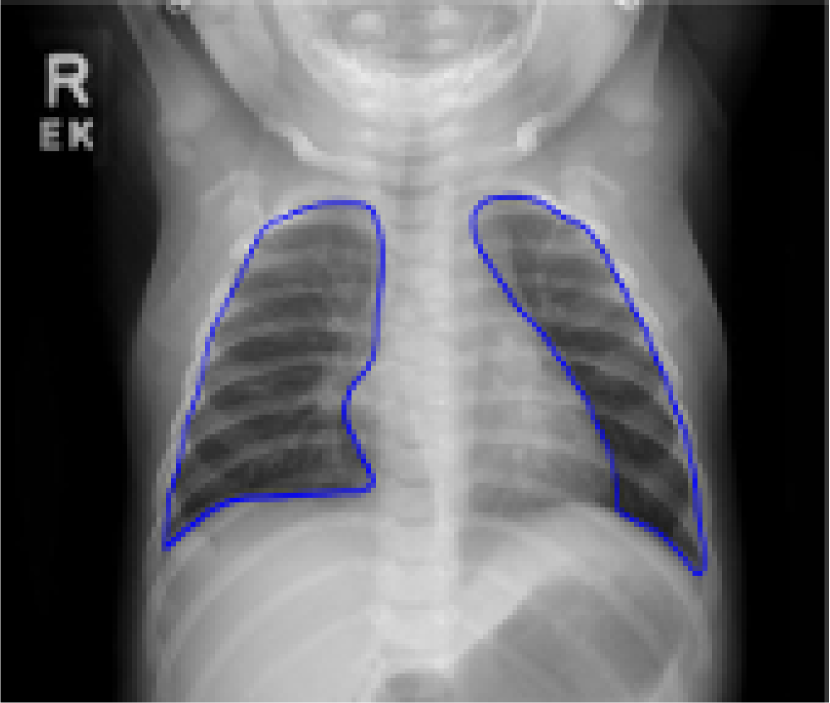

Despite tremendous advancements in tomographic imaging, chest radiography remains the most commonly used imaging modality for pulmonary analysis mainly due to its low cost, low radiation dosage, and widespread availability. Radiation dosage is of particular concern in pediatric applications, especially in neonatal intensive care units where chest radiographs (CXRs) are considered the first option for pulmonary diagnosis [1]. Lung field segmentation is the necessary initial step for image-based pulmonary analysis. Accurate delineation of lung field from CXR, however, is challenging due to ambiguous boundaries, pathologies, occultation of lung field by anatomical structures in thorax, anatomical variation of lung shapes, and size across subjects (Fig. 1). Part of the challenge in developing computer-aided diagnosis (CAD) methods, especially for pediatric cohorts, is also the anatomical shape variation of lung field that occur during growth [2, 3]. As shown in Fig. 1, pediatric cohorts have a more compliant chest wall, small thoracic cage, and relative large abdominal space. Furthermore, the diaphragm of children has smaller apposition area which has a concave shape in the posterior-anterior (PA) view CXR [3]. Therefore, existing approaches to lung field segmentation that are designed primarily for adult cohorts, are not accurate at analyzing the pediatric subjects. Although a few pilot studies such as [2] have been conducted recently to look at the age-related radiological biomarkers in lungs, no comprehensive study of pediatric lung field segmentation exists to the best of our knowledge.

The ground truth labels both including and excluding the retro-cardiac region were prepared by two fellows using the ITK-SNAP interactive software ( ) under the supervision of two expert pulmonologists. For ground truth labels including the retro-cardiac region, an overall inter-observer agreement of was observed; specifically, for CNHS data and for the JSRT and BTP data was estimated. Ground truth labels excluding the retro-cardiac region were prepared for comparative purposes with the state-of-the-art methods. To construct the statistical shape model, 144 boundary points (72 per left/right lung) with anatomical correspondences are annotated. Specifically, six manually annotated primary landmarks were initially obtained for each lung based on their distinctive anatomical appearance and ability to roughly define the shape of lung. Subsequently, equidistant secondary landmarks were estimated along the lung contour using interpolation between the primary landmarks. In order to make sure that no loss in the segmentation label accuracy has occurred due to the interpolation, the accuracy of the proposed interpolation method was evaluated using the Dice coefficient score (DCS) between the manual ground truth and the landmark-based interpolated contour. A mean DCS of was obtained for our dataset. Further details on our manual landmarking approach can be found in [31].

Fig. 9 presents the qualitative results of performing the lung segmentation using the proposed pipeline (ESL+MaShDL). The figure provides a visual insight on how inclusion of retro-cardiac region results in the segmentation label that is independent to the shape and structural changes in the close-by anatomical structures such as heart. For comparison purposes, similar qualitative results for the lung field labels obtained using the method proposed in [11] are provided in Fig. 10. As predicted before, the shape specificity is not preserved for the lung field labels obtained using [11]. This is further evident through the results presented in Table II. Moreover, unlike the proposed method, the U-net architecture uses an overlapping-based objective function (e.g., cross-entropy) which provides satisfactory results in cases with reduced shape variability. However, in the particular case of thoracic radiographs, the lung field labels without retro-cardiac space present higher shape variability than those observed when including this region. This could be a possible explanation of a slightly better overlapping-based performance (i.e., Overlap and DSC) by U-Net [11] when including the retro-cardiac space than without including it.